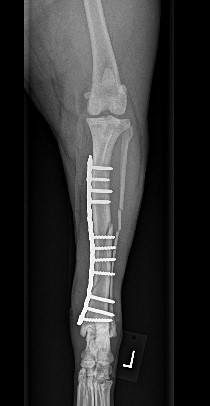

ADVANCED VETERINARY ORTHOPEDIC SERVICES

Our world-class, board-certified veterinary surgeons are dedicated to providing the most advanced canine orthopedic veterinary surgery and musculoskeletal assessment to ensure your beloved pet receives the most appropriate and comprehensive veterinary treatment available.